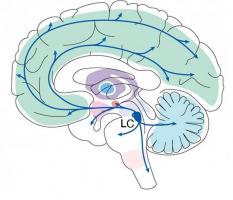

Actualité publiée le 11/11/2021LOCUS COERULEUS : Un centre clé de l’apprentissage ?

Actualité publiée le 16/09/2021